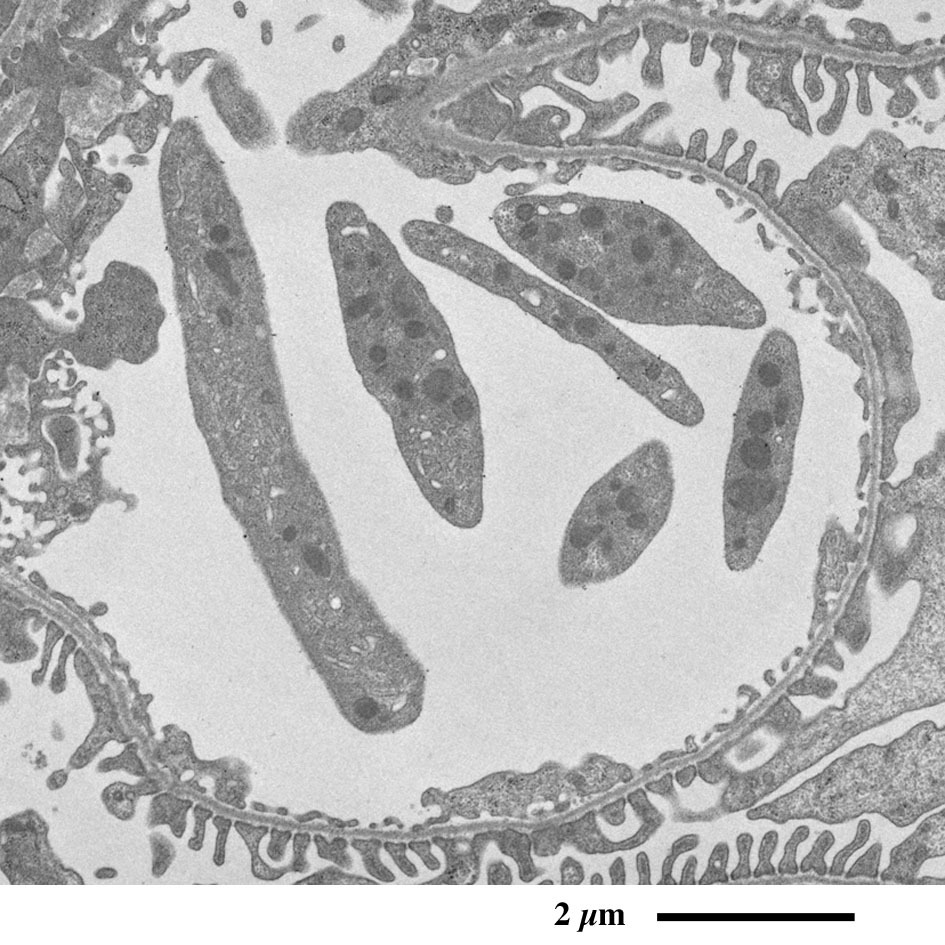

【 超薄切片の透過型電子顕微鏡画像 】

Transmission electron microscopic image of ultrathin section

近位尿細管

原尿に含まれるグルコースや電解質、水など身体に必要な物質を再吸収するため、

上皮細胞の頂上部に微絨毛が並んで表面積を増大しています。

近位尿細管上皮細胞